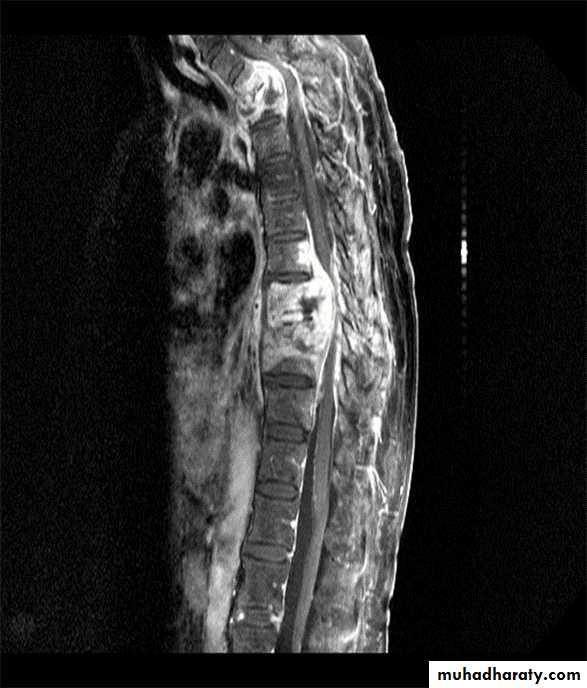

Sagittal MR image of the thoracic spine

demonstrates destruction of the intervertebral disc at the point where the paraspinal widening is maximal and this change is associated with alteration ofsignal from the vertebrae.